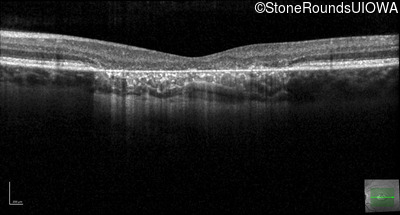

This 22 year old man had macular abnormalities noted incidentally at a routine eye exam at age 19. Since then, he has experienced a gradual loss of acuity particularly in the left eye.